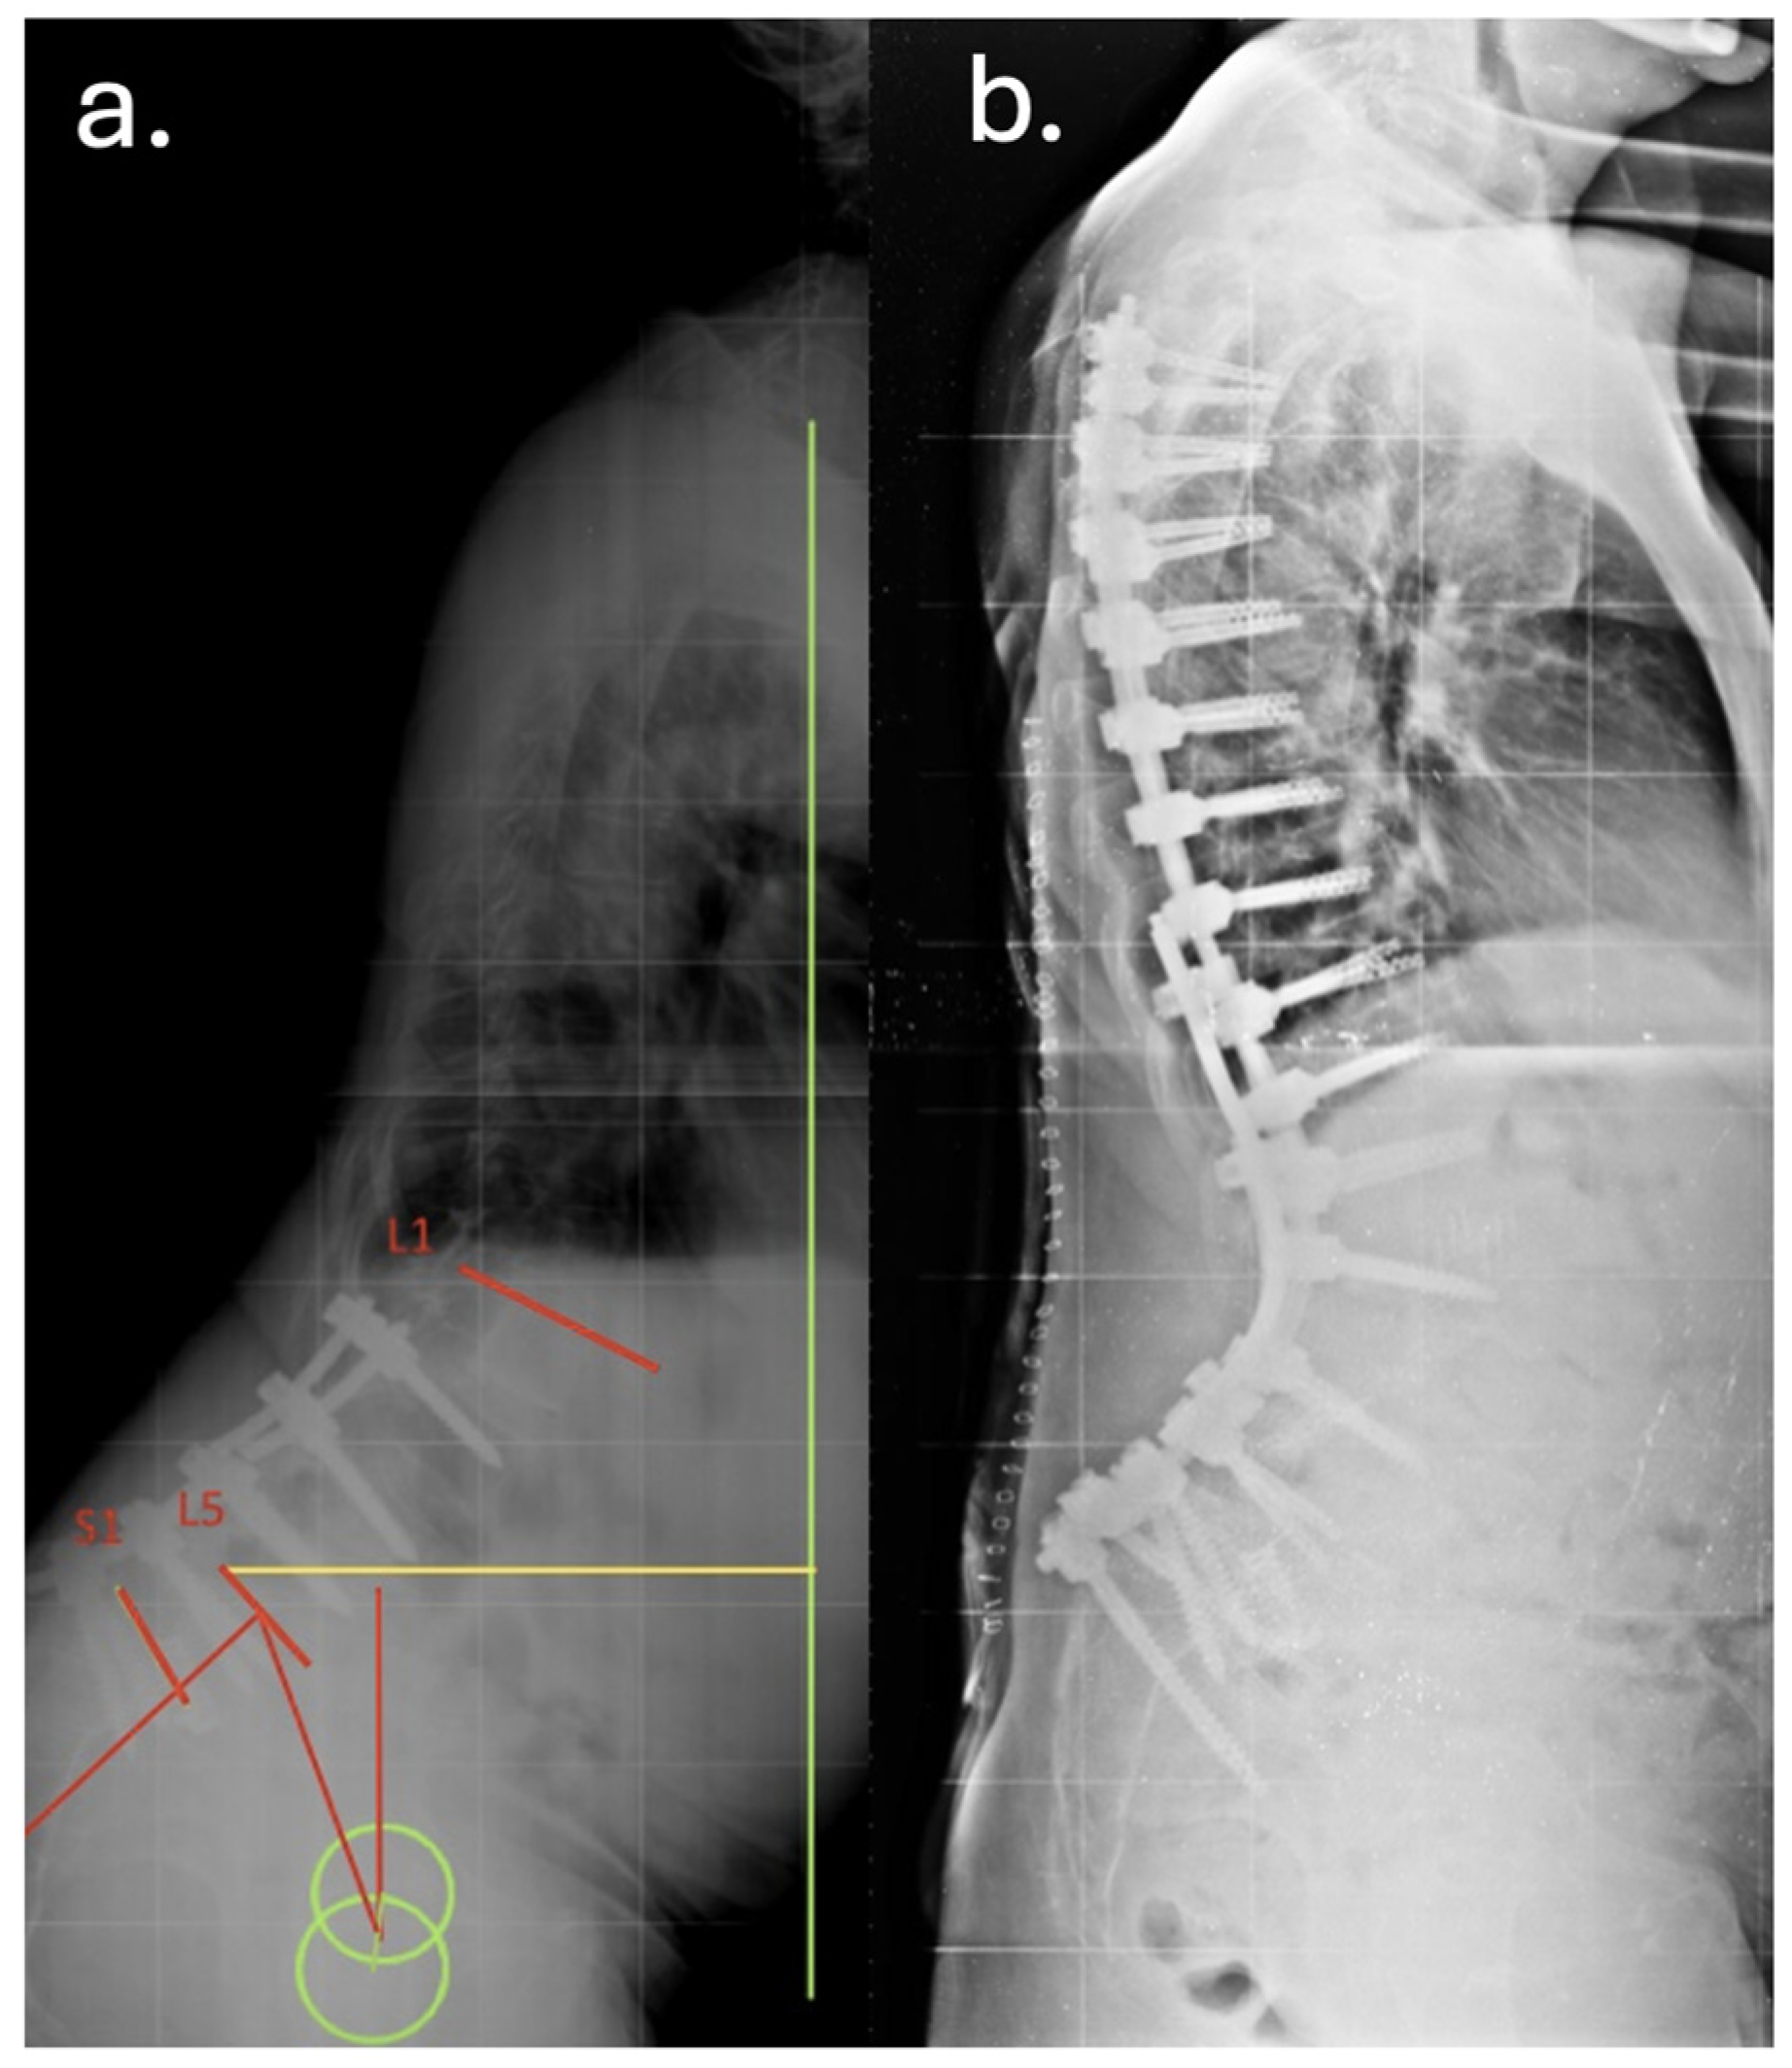

3. Case Report

| Year | Event |

|---|---|

| Dec 2010 | Posterior decompression and L5–S1 fusion |

| Apr 2012 | Posterior extension of fusion to L3 for junctional failure |

| Nov 2014 | Extreme lateral interbody fusion (XLIF) at L3–L4 and L4–L5 |

| Jun 2016 | Major revision from T7 to pelvis with bilateral iliac fixation |

| Aug 2016 | Postoperative infection (Acinetobacter baumannii XDR), multiple antibiotic courses |

| Dec 2019 | Removal of left iliac and T4–T5 screws, new fixation at T2–T3 with 4-rod construct |

| Jan 2020 | Rotational musculocutaneous flap for soft tissue coverage |

| Feb 2022 | Diagnosis of sacral insufficiency fracture (CT: left sacral ala right ilio-pubic branch fracture, with loosening of iliac screws) |

| Sep 2022 | Surgical debridement, rod shortening, V-Y fasciocutaneous flap |

| Mar 2025 | Removal of fractured proximal thoracic screws; cultures positive for Staphylococcus epidermidis and Ralstonia pickettii |

| May 2025 | Stable condition on suppressive antibiotics; no further revision indicated |